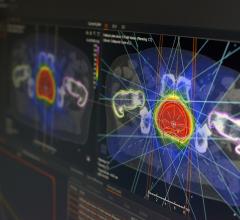

Varian Medical Systems will be exhibiting its complete line of hardware, software, and applicators for HDR and LDR brachytherapy, including the VariSource iX, GammaMedplus iX and the GammaMedplus 3/24 iX HDR afterloaders, the BrachyVision treatment planning system plus the Vitesse module for using transrectal ultrasound (TRUS) images as the basis for a prostate cancer treatment plan. For LDR treatments, the VariSeed treatment planning system is a leading system for this highly specialized form of brachytherapy.